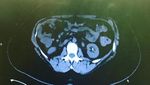

Biasanya, akan dilakukan pemeriksaan mulai dari tes urine, pengambilan sampel darah, dan pemindaian dengan menggunakan USG atau rontgen.(Foto: Instagram @artcore_st)